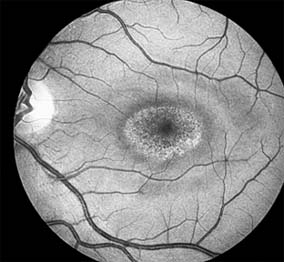

The cone-rod dystrophies constitute a relatively rare group of disorders that may be regarded as a single entity showing variable expressivity. Most cases are sporadic, but familial cases are usually transmitted by an autosomal dominant inheritance pattern. Cone-rod dystrophy is characterized by predominant involvement of the cone photoreceptors with progressive color vision defects and associated loss of visual acuity. A bilateral and symmetric bulls-eye pattern of depigmentation and a corresponding zone of hyperfluorescence surrounding a central nonfluorescent spot (similar to that seen in chloroquine retinopathy) are the most commonly described biomicroscopic and angiographic changes in these patients (Figure 10-15). As the disease progresses, the electroretinogram shows marked loss of cone function associated with a slight to moderate loss of rod function. Histopathologic study shows absence of macular and paramacular photoreceptors, and there is associated pigment epithelium degeneration.

Figure 10-15

Figure 10-15: Cone dystrophy with depigmentation and a bull's-eye pattern to the macula.